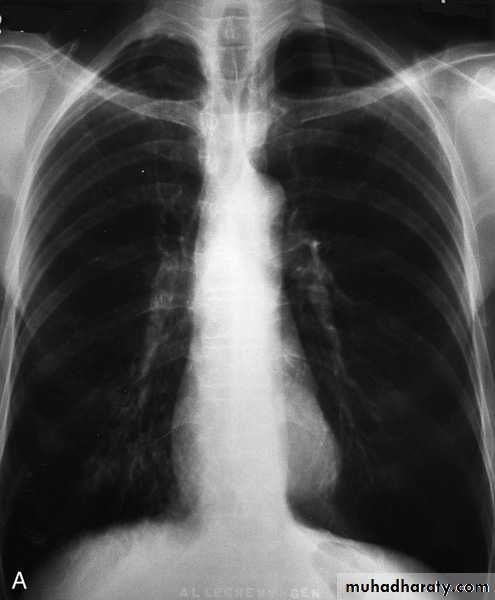

Investigations Imaging

Chest X-ray: typical changes of emphysema include paucity of parenchymal markings, hyper-translucency and bulae. Increasing lung volume and flattening of diaphragm suggest hyperinflation.